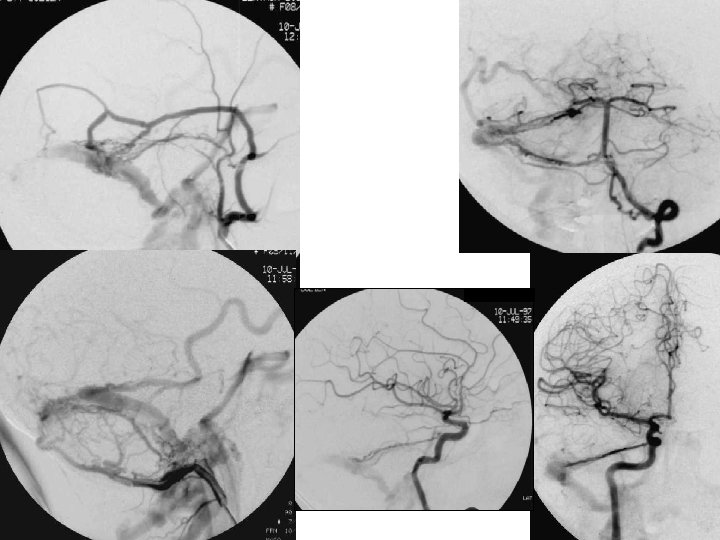

Angiographie • Indications très limitées : – contre-indications et insuffisances de l ’IRM (et de l’angioscanner) • injections globale et sélectives • vues de face, de profil et obliques • temps tardifs 73

Angiographie • Occlusions veineuses (absence d ’opacification) • Retard circulatoire (stagnation) • Circulation de suppléance – veines corticales en « tire-bouchon » – veines trans-cérébrales – veines extra-cérébrales 74

Angiographie • Faux positifs • Flux de lavage (étudier l ’injection globale et les autres axes) • Hypoplasie ou agénésie du sinus latérale (recher la gouttière osseuse, analyser le type d ’arrêt d ’opacification) 75

76

77